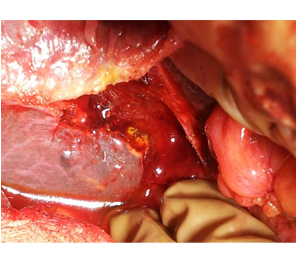

HCC in a non cirrhotic liver

Intra Operative image after right hepatectomy